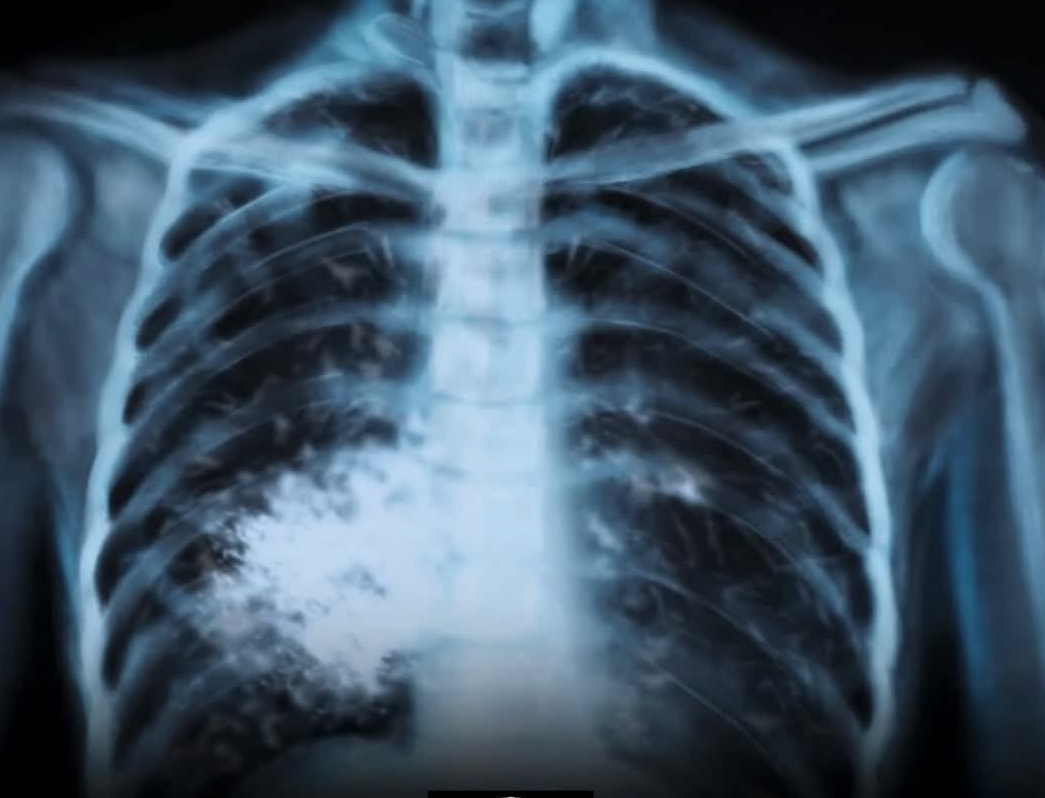

Биомаркерите са ключът към правилното лечение на рака на белия дроб

Ракът на белия дроб продължава да бъде едно от най-смъртоносните онкологични заболявания. Всяка година над 2 милиона души по света получават тази диагноза, а около 1.8 милиона умират от нея. В България заболяването засяга 16.6% от мъжете и близо 7% от жените, което го нарежда сред трите най-чести онкологични диагнози при двата пола. Докато в повечето страни от Европейския съюз смъртността намалява, у нас тенденцията е обратна – случаите се увеличават, особено сред мъжете. Едва 8% от българите преживяват повече от пет години след диагнозата, при 15% средно за ЕС, като късното откриване на заболяването остава основна причина за лошата прогноза. Повечето пациенти се диагностицират в трети или четвърти стадий.